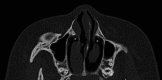

Figure 3. Axial view of the CT scan of the sinus showing the bilateral agenesis of the head of the inferior turbinates

The asterisk represents the agenesis of the head inferior turbinate. CT: computed tompgraphy